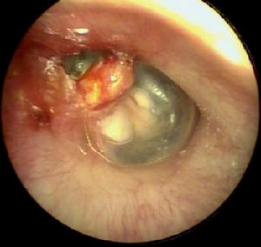

患者可以流脓或不流脓,脓一般有特殊的臭味。可以有较重的传导性耳聋或混合性耳聋。查体可见鼓膜松弛部、紧张部后上方穿孔,或边缘性穿孔,穿孔内可见胆脂瘤皮或肉芽。影像学:CT示上鼓室、鼓窦或乳突骨质破坏,边缘整齐。